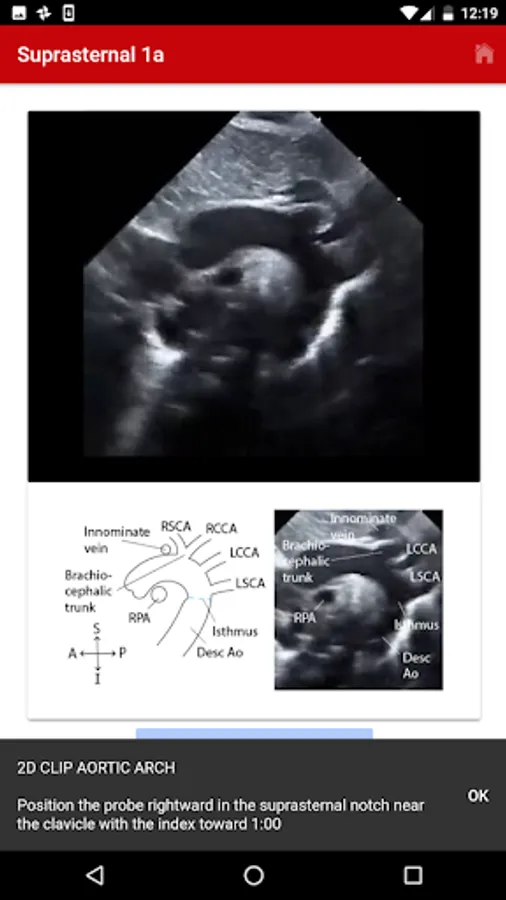

4. Suprasternal

The exact images and the order in which the images and views are obtained varies by institution. Each protocol (subcostal, parasternal, apical or suprasternal) can be followed in order by clicking on the next tab at the bottom of the page or you can click on an individual numbered view within the protocol list to be taken directly to that view. The name of the view and instructions will pop-up automatically at the bottom of the page. The instructions and additional notes can also be found in the “NOTE” button at the bottom of the page.